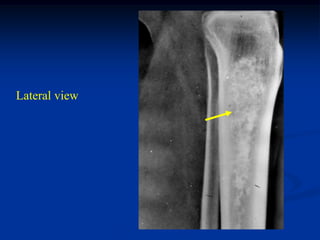

The periosteal chondroma has the same basic pathology as the

enchondroma except that it occurs on the surface of a tubular

bone. It can occur as a hamartomatous process in growing patients

but as with enchondroma it is usually asymptomatic and growth

stops at bone maturity. The lesions are found in large bones, such

as the humerus and femur, and in the small bones of the hand and

foot. Radiographically one sees slight erosion into the adjacent

cortex but the lesion will not penetrate into the medullary canal.

There will be a sclerotic response at the base that extends around

the periphery of the lesion taking on the appearance of a blister

on the surface of the bone with matrix calcification seen mainly

at the periphery but found also in the central area. The lesions

usually stop growing before they reach the upper limit of 3-4 cm

in diameter. If growth continues beyond this, one must strongly

consider the possibility of a peripheral surface type chondrosarcoma

that would continue to grow after bone maturity.